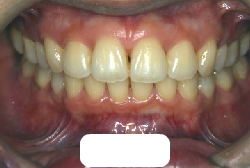

叢生(そうせい)

凸凹な歯並びのことを叢生といいます。矯正歯科に来院する患者様の主訴の中で、最も多いのが「配列の凸凹を真っ直ぐにしたい」というものです。歯の大きさと顎の大きさの調和がとれていないことが原因です。

凸凹を主体としたケースの場合、当院の平均治療期間は18ヶ月ですので、このケースは少し長めに経過しました。理由の一つは凸凹の程度がかなり重症だったと言うことですが、もう一つは、右下第2大臼歯が45度くらい前傾していたため、それを整直化させるために時間を要したと考えています。いずれにしても最終結果は大変よい状態と思います。

治療前は並びが乱れて見た目が悪いというのはもちろん問題ですが、歯科医学的に一番困るのは噛み合わせが悪いという点です。上下の犬歯(3番目の歯)は、上下的に離れた位置にあるため接触することができません。つまり歯としては存在していても、歯としては機能していないということです。